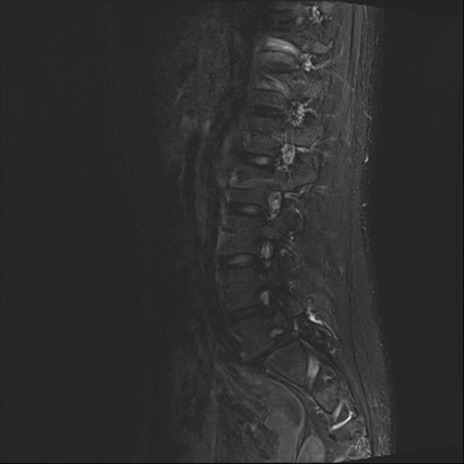

【整形】TIPS症例4 腰椎MRI STIR(矢状断像)

腰椎MRI

T2WI(矢状断像)